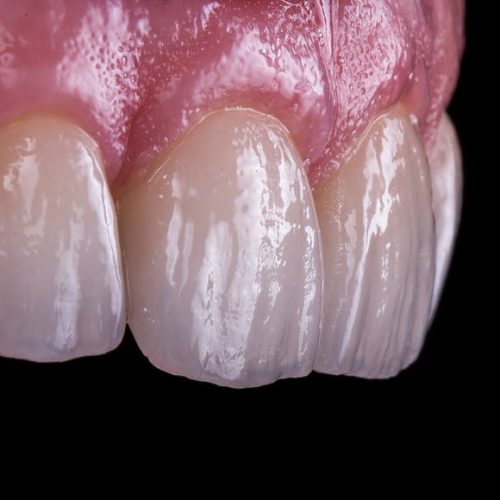

ApprofondisciPROTESI DENTARIA

La protesi dentaria si occupa di ripristinare o sostituire elementi dentali mancanti con manufatti protesici costruiti dal nostro laboratorio odontotecnico che provvede a realizzarli su precisa indicazione dell’odontoiatra.